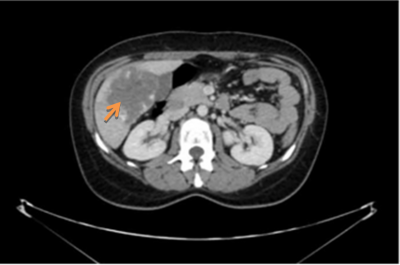

בבדיקות מעבדה: תפקודי הכבד לרוב תקינים, אך תיתכן עליה קלה ברמת האנזימים. האבחנה מתבצעת על ידי טומוגרפיה ממוחשבת (תמונה 26.10 ) או תהודה מגנטית (תמונה 27.10) כך שבדרך כלל אין צורך לקחת ביופסיה. באולטרה-סאונד ניתן להדגים גוש בכבד (תמונה 28.10).

קשר לגלולות למניעת הריון - קיים קשר כלשהו בין נטילת גלולות למניעת הריון לבין הופעת השאת. אך בגלל שאין הוכחות חותכות לקיום קשר זה וגם לא ברורה משמעותו, אין מניעה להמשיך ליטול גלולות למניעת הריון או הורמונים גם בנשים עם FNH, אולם קיימת המלצה למעקב על ידי בדיקות הדמיה כל 6-12 חודשים.

ההמלצות - אם אכן אובחן הגידול על ידי בדיקות הדמיה כמתואר לעיל, כדאי לעשות מעקב 3 ו- 6 חודשים לאחר האבחנה (גם כן על ידי בדיקות הדמיה) כדי להראות שהגידול נשאר יציב בגודלו ושמאפייניו אכן שפירים, ולאחר מכן אין צורך בהמשך מעקב, למעט נשים הנוטלות גלולות שמומלץ אצלן המשך מעקב, כמתואר לעיל. כלומר, כל עוד הגידול נשאר יציב בגודלו, אין צורך בטיפול.

במקרים נדירים ביותר של גידולים גדולים או כאלה הגורמים לסימפטומים, יש צורך בניתוח לכריתת השאת (תמונה 8.10).